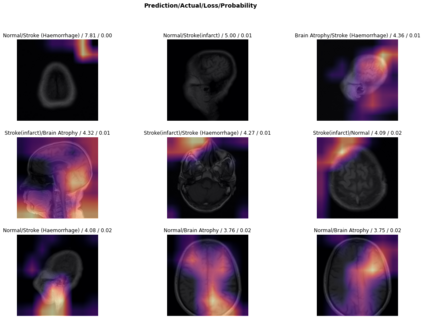

Magnetic Resonance Imaging (MRI) is a principal diagnostic approach used in the field of radiology to create images of the anatomical and physiological structure of patients. MRI is the prevalent medical imaging practice to find abnormalities in soft tissues. Traditionally they are analyzed by a radiologist to detect abnormalities in soft tissues, especially the brain. The process of interpreting a massive volume of patient's MRI is laborious. Hence, the use of Machine Learning methodologies can aid in detecting abnormalities in soft tissues with considerable accuracy. In this research, we have curated a novel dataset and developed a framework that uses Deep Transfer Learning to perform a multi-classification of tumors in the brain MRI images. In this paper, we adopted the Deep Residual Convolutional Neural Network (ResNet50) architecture for the experiments along with discriminative learning techniques to train the model. Using the novel dataset and two publicly available MRI brain datasets, this proposed approach attained a classification accuracy of 86.40% on the curated dataset, 93.80% on the Harvard Whole Brain Atlas dataset, and 97.05% accuracy on the School of Biomedical Engineering dataset. Results of our experiments significantly demonstrate our proposed framework for transfer learning is a potential and effective method for brain tumor multi-classification tasks.